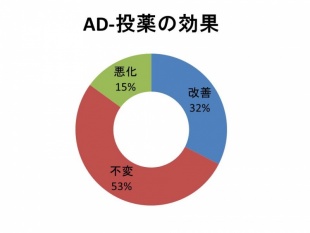

Q 認知症の薬は効果ありますか?

認知症の薬は現在4種類あります。当院で認知症の診断がされて投薬を始めた方のアンケートです。

薬を飲むことで32%の方が改善しました。53%の人が変化はみられないものの症状は進行していないようです。

認知症は少しずつ進行するものですので、認知症の薬を飲むことで8割以上の方に何らかの効果が認められるようです。早めに薬を始めることも大切と思われます。